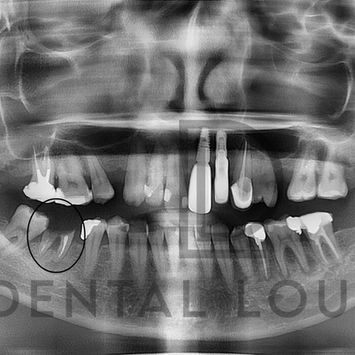

Surgical Removal of Retained Roots – Tooth #46

Patient attended for management of a fractured lower right molar (tooth #46) with retained roots.

Fractured with retained roots

Previously root-filled

Two-rooted tooth

Wide and flattened mesio-buccal (MB) and disto-buccal (DB) roots

Periapical lesion noted at apex of tooth #41

Deep filling extending to the pulp

Periapical involvement affecting neighbouring teeth